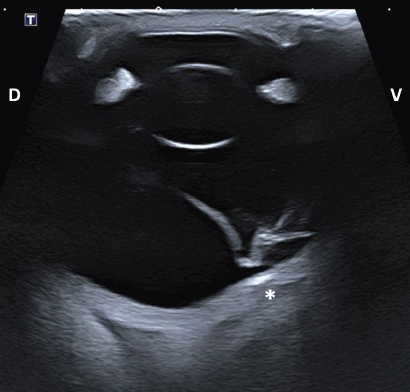

Intraocular lesions found on US and MRI of both horses were consistent with the ophthalmic examination. Complete RD OS and hyperechoic vitreous floaters OU were noted on US (Fig. 4). RD was also evident OS on MRI, more conspicuously on T2W and FLAIR sequences. In T2 sequences, the detached retina was identified as a V-shaped membrane of intermediate signal inside the hyperintense vitreous and reaching the optic disk (Fig. 5A), while it was slightly hyperintense in comparison to the hypointense vitreous chamber on FLAIR acquisitions (Fig. 5B). There was a subjectively abnormal positioned optic disk OU on US and MRI, suggesting ectopic ONH. OS was flattened at the level of the ONH in both horses. Except for a subarachnoid emphysema due to postmortem changes, the brain looked otherwise normal on MRI. Based on US, the axial globe length measured 39.2 mm OS and 41.5 mm OD of case 1 and 45 mm OU in case 2.

Fig. 3. Electroretinography results of case 1 with normal traces of rod (blue) and combined rod-cone response (red and black) OD (A) and a flat tracing OS (B).

Fig. 4. Transpalpebral ultrasonographic image OS of case 1 in a vertical longitudinal axis. A “seagull sign” is visible in the vitreous, consistent with RD. * Note the depression at the caudoventral aspect of the globe, in the area of the optic disk (not visible on this isolated image). D: dorsal; V: ventral.